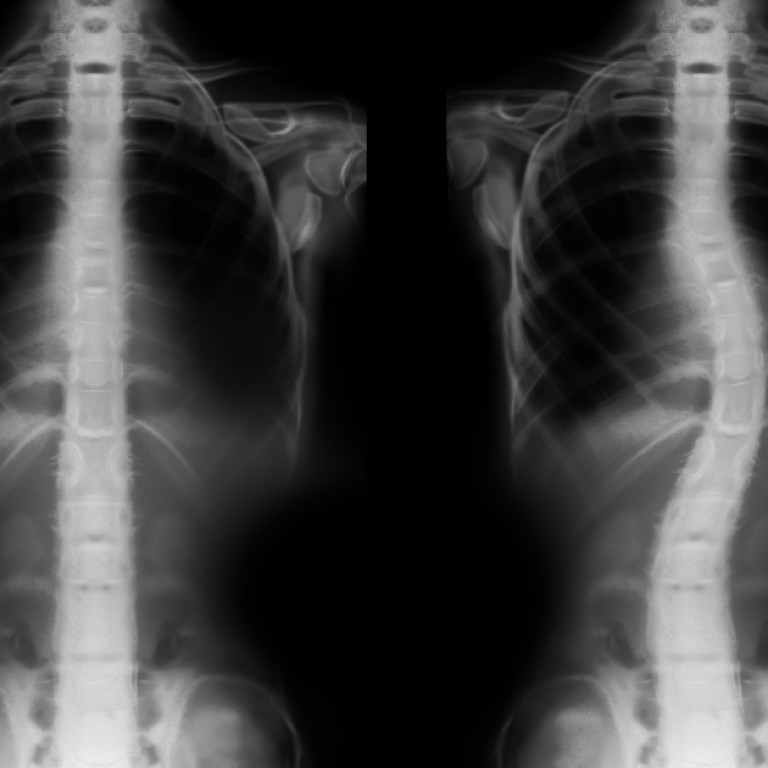

Omurga sağlığı çoğu zaman günlük hayatın içinde fark edilmeyen fakat yaşam kalitesini önemli ölçüde etkileyen bir konudur. Skolyoz …